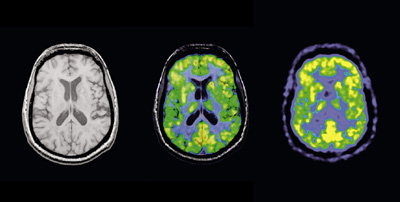

Teljesen új „betekintést” nyújt az emberi agyba a mágnesrezonanciás tomográfiát (MR) és a nukleáris medicina egyik képalkotó eljárását, a pozitron-emissziós tomográfiát (PET) kombináló Siemens-prototípus. Szakértők úgy vélik, hogy ez az egyedülálló új berendezés javítja az Alzheimer-kór diagnosztizálásának lehetőségét a korai szakaszban, valamint az orvosok számára lehetővé teszi a szélütéses (stroke) páciensek állapotának gyorsabb felmérését és a megfelelő terápia meghatározását. A tübingeni egyetem és a memphisi Tennessee egyetem (USA) orvosi karának doktorai a közelmúltban felvételeket készítettek az új berendezéssel az emberi agyról. Az MR technika nagy felbontóképességével és a lágy szövetekről adott éles kontrasztú képeivel járul hozzá a kombinált eljáráshoz, míg a rendkívül érzékeny PET részlet-gazdag képet ad az agy olyan régióiról, melyek fokozott anyagcsere-tevékenységet mutatnak. A prototípust az év második felében tovább tesztelik Németországban.

A PET vizsgálat során a páciensbe nagyon kis dózisban radioaktív folyadékot fecskendeznek, amely olyan sejtekben gyülemlik fel és bocsát ki pozitron-sugárzást, amelyeknek megnőtt az anyagcsere-értéke. Amikor a pozitronok elektronokkal ütköznek, megsemmisülnek, és gamma kvantumok keletkeznek. Ezeket a kvantumokat regisztrálja a műszer detektora, amely az adatokból háromdimenziós, rétegelt képet alkot. A Siemens Orvostechnika (Medical Solutions, Med) rendkívül gyors működésű és érzékeny lavina-fotodiódákat alkalmaztak detektorként. Ezek érzéketlenek a tandem berendezés MR-„felének” erős (3 Tesla) mágneses térerejére, amelynek az a nagy, kb. 0,2 mm-es felbontóképességét köszönheti. A két készülék által generált képeket a berendezésben szuperponálják, és így keletkeznek az eddig soha nem látott képek.